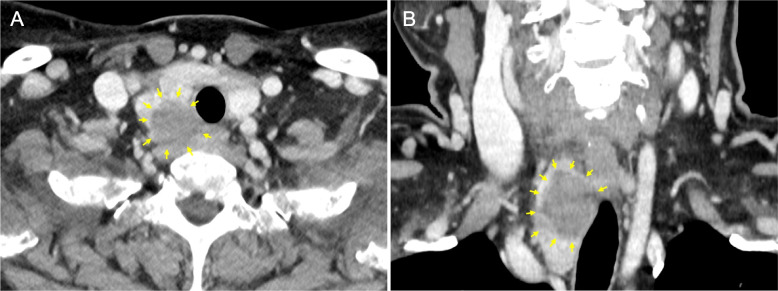

Case presentation: A 59-year-old Japanese female presented with hoarseness and pharyngeal discomfort. Endoscopic examination revealed fixation of the right vocal cord, presumably due to right RLN palsy. Ultrasonography and computed tomography showed an ill-defined thyroid mass lesion in the right lobe, strongly suggestive of malignancy, although repeated aspiration cytology revealed no suspicion of malignancy. Intraoperatively, because the right RLN was found to be entirely embedded within the hard mass lesion and completely unresponsive to nerve integrity monitoring, the nerve was unavoidably excised along with the right lobe. Histopathology led to the final diagnosis of nodular goiter, wherein the resected RLN was severely degenerated and disrupted due to intense chronic inflammation accompanied by perineural fibrosis.